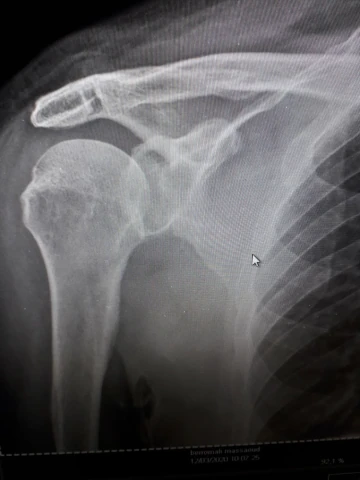

Fracture épaule

img